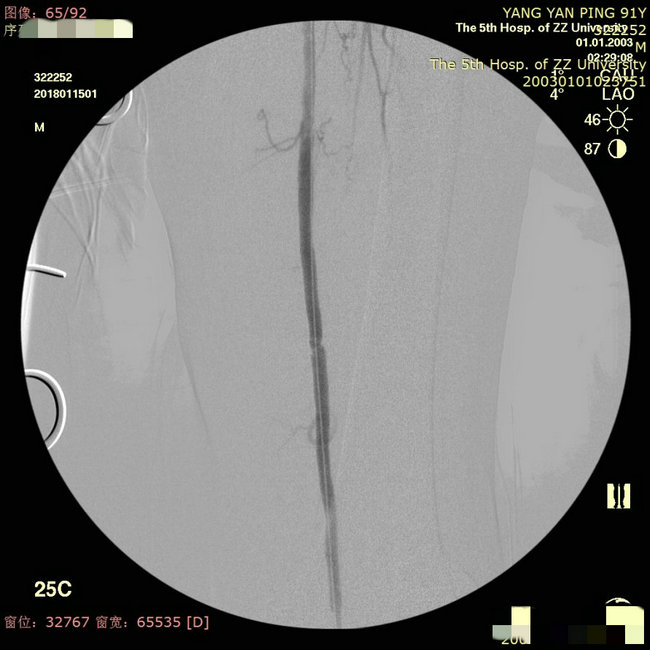

▲ 释放支架后造影显示血管恢复通畅